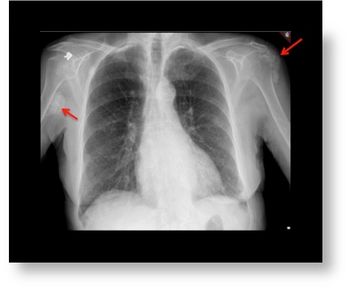

A 74-year-old female presents with palpable lump over the right axillary region.